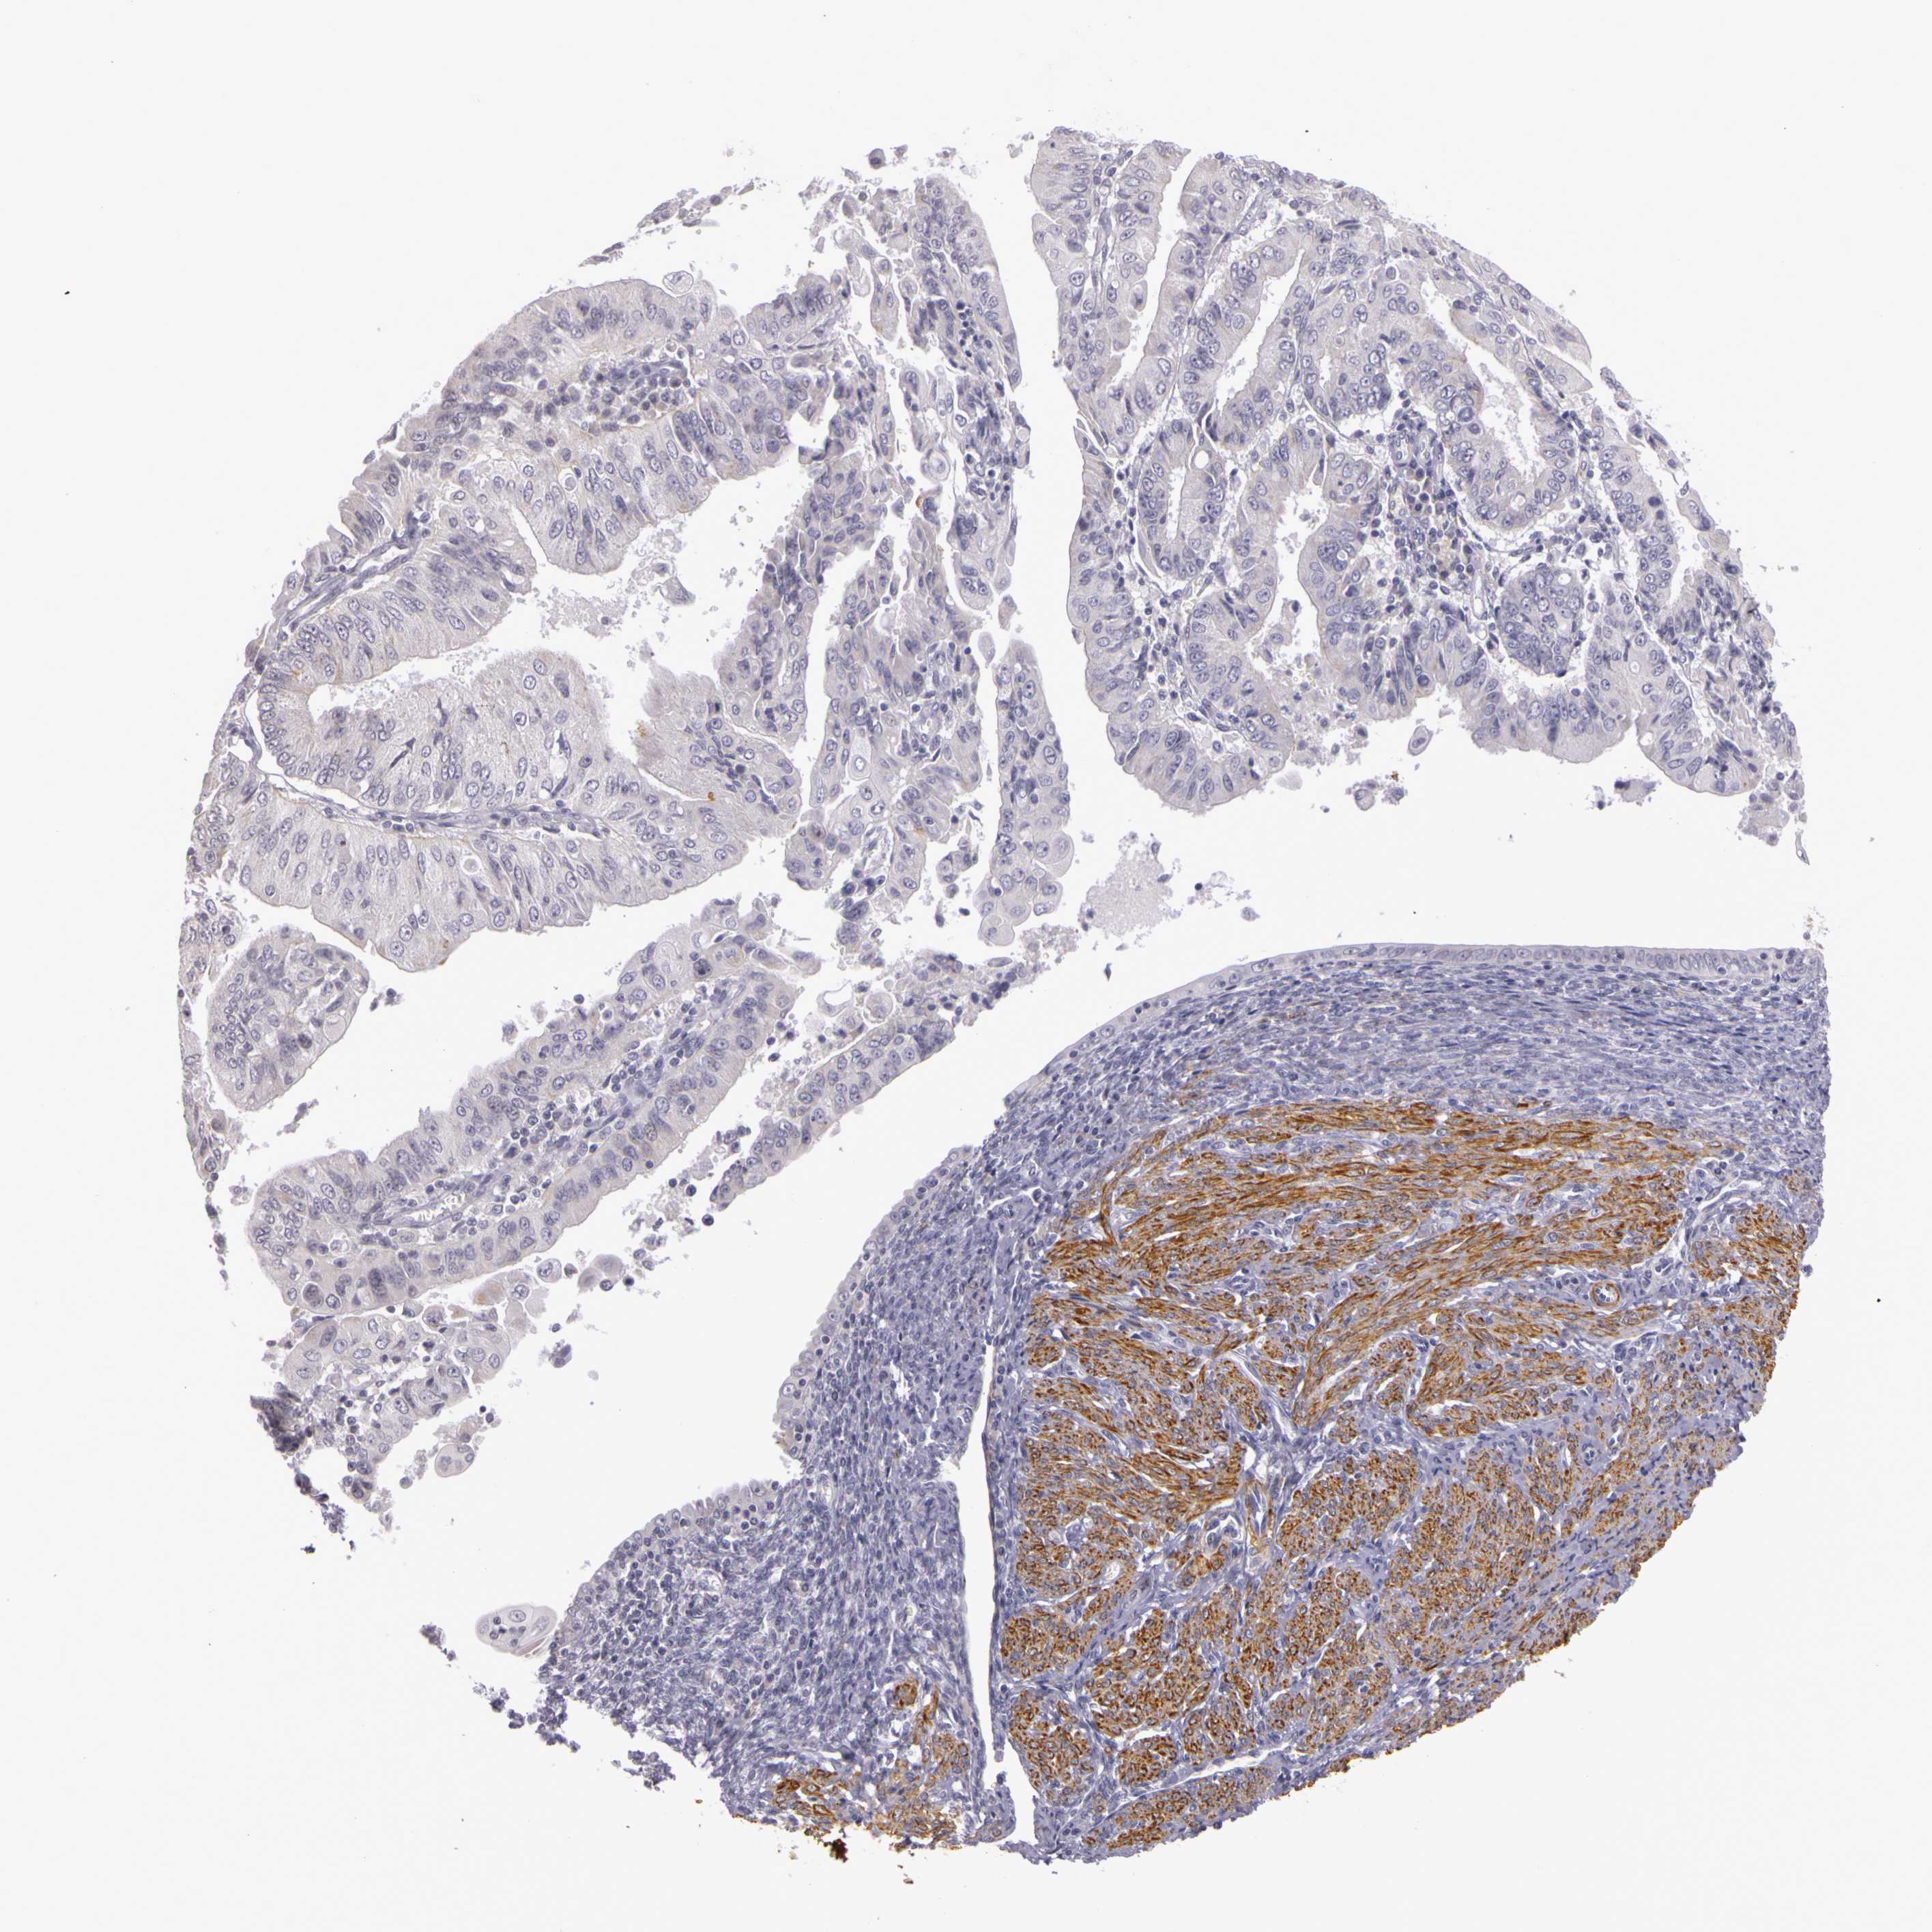

ENDOMETRIAL CANCER - Protein expressioni

A mouse-over function shows sample information and annotation data. Click on an image to view it in a full screen mode. Samples can be filtered based on level of antibody staining by selecting one or several of the following categories: high, medium, low and not detected. The assay and annotation is described here.

Note that samples used for immunohistochemistry by the Human Protein Atlas do not correspond to samples in the TCGA dataset.

Antibody stainingi

Antibody staining in the annotated cell types in the current human tissue is reported as not detected, low, medium, or high, based on conventional immunohistochemistry profiling in selected tissues. This score is based on the combination of the staining intensity and fraction of stained cells.

Each image is clickable and will lead to virtual microscopy that enables deeper exploration of all samples and also displays staining intensity scores, fraction scores and subcellular localization as well as patient and tissue information for each sample.

Antibody HPA001397

Antibody HPA012497

Staining

High

Medium

Low

Not detected

Intensity

Strong

Moderate

Weak

Negative

Quantity

>75%

75%-25%

<25%

None

Location

Nuclear

Cytoplasmic/membranous

Cytoplasmic/membranous,nuclear

Adenocarcinoma, NOS